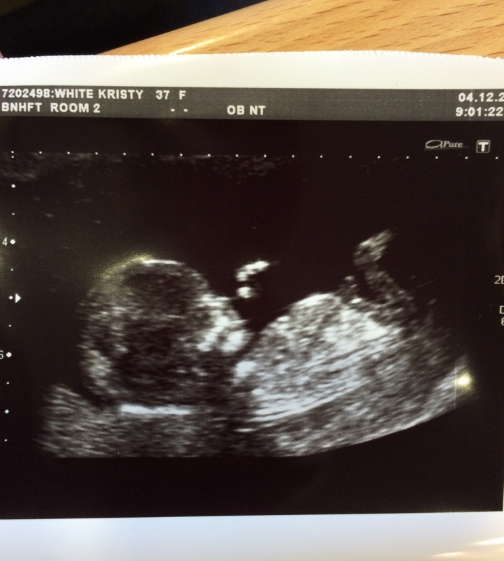

Wonderfully exciting news - the Acre in Hampshire clan is growing! This will be our first little nipper, which makes it all the more tremendous...